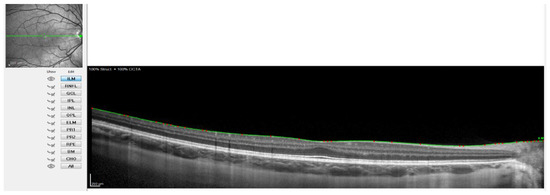

- Rahman, W.; Chen, F.K.; Yeoh, J.; Patel, P.; Tufail, A.; Da Cruz, L. Repeatability of Manual Subfoveal Choroidal Thickness Measurements in Healthy Subjects Using the Technique of Enhanced Depth Imaging Optical Coherence Tomography. Investig. Ophthalmol. Vis. Sci. 2011, 52, 2267–2271. [Google Scholar] [CrossRef]

- Spaide, R.F.; Koizumi, H.; Pozonni, M.C. Enhanced Depth Imaging Spectral-Domain Optical Coherence Tomography. Am. J. Ophthalmol. 2008, 146, 496–500. [Google Scholar] [CrossRef] [PubMed]